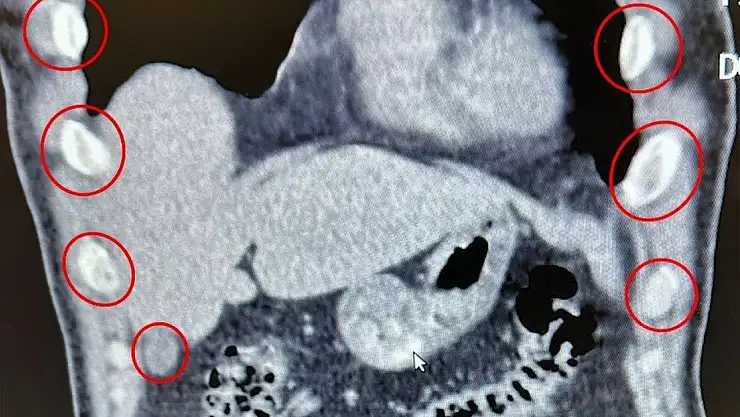

Bitlis İl Emniyet Müdürlüğü Narkotik Suçlarla Mücadele Şube Müdürlüğü ekipleri, uyuşturucu ile mücadele kapsamında önemli bir operasyona imza attı. Tatvan ilçesinde durdurulan bir otobüste yolcu olarak seyahat eden yabancı uyruklu 2 kişi gözaltına alındı. Şahısların yapılan tıbbi müdahalesinde, yuttukları 136 kapsül halinde toplam 1 kilo 48 gram metamfetamin ele geçirildi.